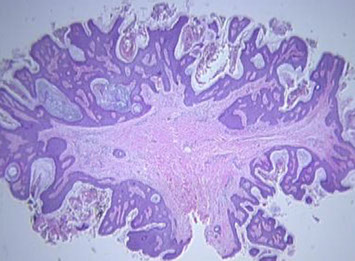

Syringocystadenoma Papilliferum (SCAP)

aka papillary syringadenoma

b9 sweat gland proliferation that arises in the middle of a nevus sebaceus

- warty tumor of scalp, neck, and face that can occur at any age

- clinically is a slow growing or recent change in a brithmark, may be crusty and start to bleed

- 1/3 have adjacent nevus sebaceus, 10% with adjacent BCC

- malignant counterpart is syringocystadenocarcinoma papilliferum

Micro: glandular papillary prolif connected to skin surface

- has ducts that look similar to sweat ducts sometimes, which are lined by cuboidal cells, that eventually empty to skin surface

- dense plasma cell infiltrate in the dermis, or in the middle of the papillary structures